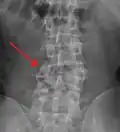

A burst fracture of L4 as seen on CT -